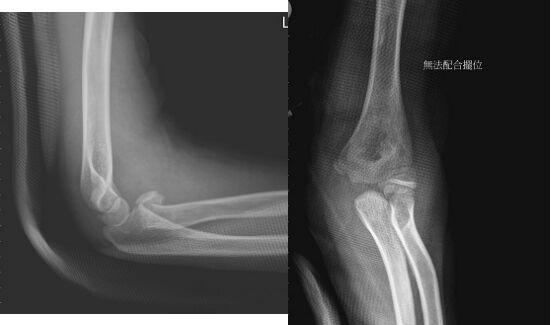

54.10歲男童今日下午爬樹時不慎掉落左手撐地,因左手肘腫脹且無法正常屈伸,其X光如附圖所示, 下列敘述何者正確?(A)X光顯示左側橈骨幹骨折且位移明顯(B)骨折受傷機轉為手掌著地,肘伸直且前臂為旋後位,橈骨頭擠壓肱骨造成(C)該骨折為關節內骨折,該患者需良好復位才能維持肘關節活動角度(D)復位後夾板固定且保持肘關節屈曲45度固定約3週